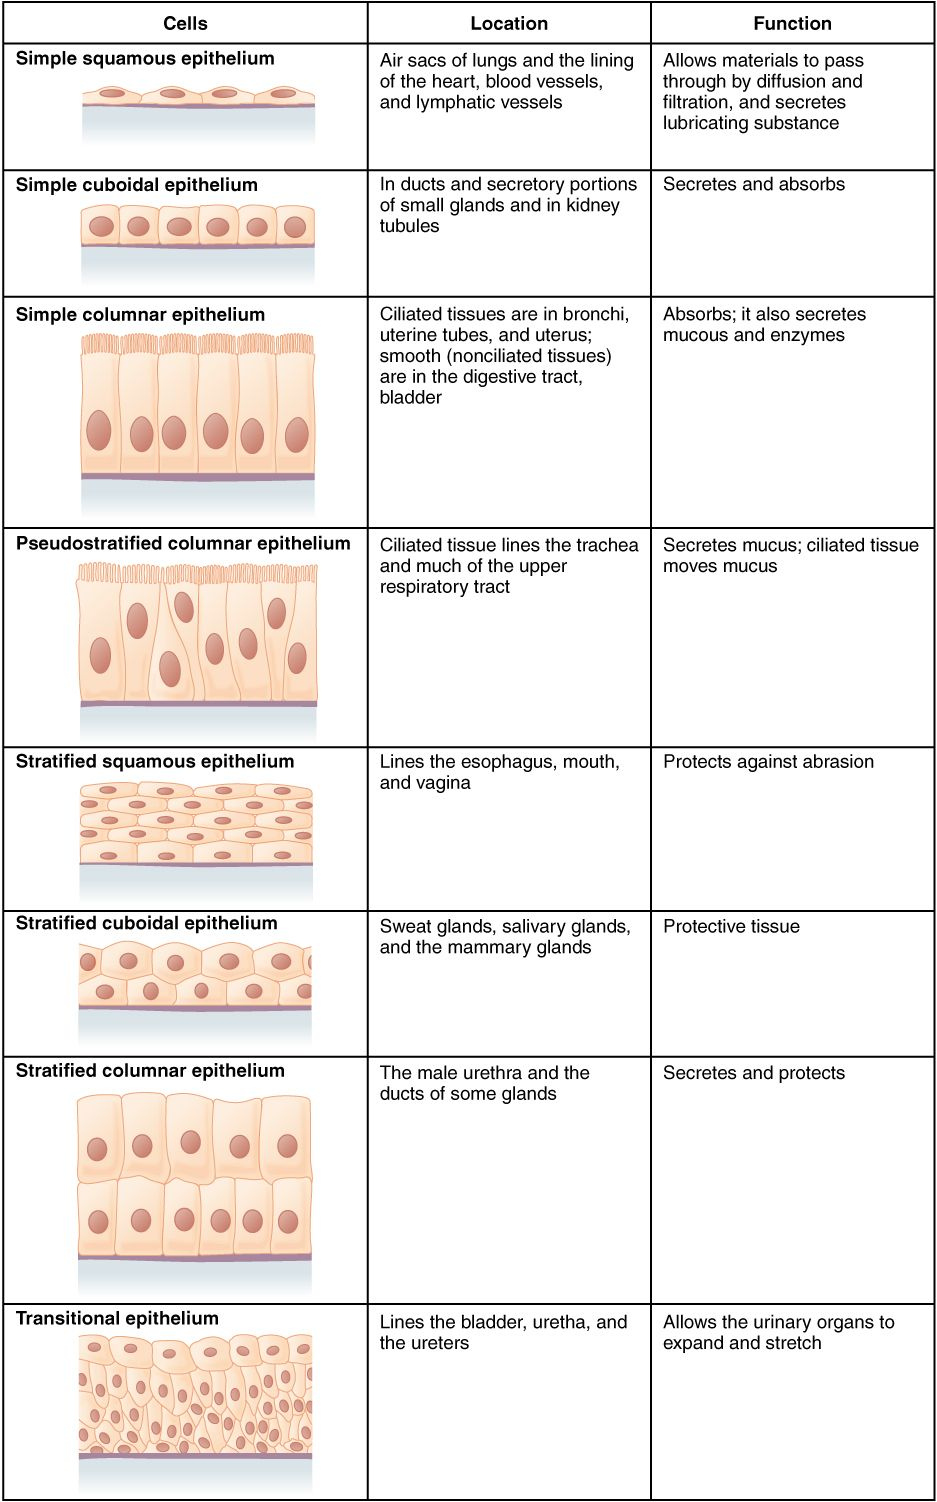

Anatomy worksheets help you discover the anatomy of various body organs. You can learn the heart’s structure and also function. For example, you can learn about the heart’s atria, which are the chambers that provide the heart with blood. You can also learn about the mitral valve, which shields the opening in between the left room and also the ventricle.

Anatomy worksheets are also helpful for pupils to discover the heart. They can learn the functions of heart muscular tissues and just how they impact the heart’s outcome. The heart has 2 valves, the left mitral shutoff and the appropriate tricuspid shutoff. Besides, they can learn more about the blood flow and also its components.